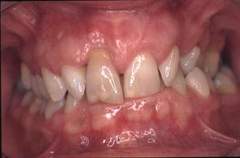

Se ocupa cu indreptarea pozitiei dintilor si a rapoartelor dintre acestia dar si a rapoartelor dintre oasele maxilare. Este foarte important sa se corecteze pozitia dintilor nu numai din motive estetice ci si functionale. Dintii inghesuiti nu pot fi igenizati corect si in timp se cariaza sau apar probleme parodontale. Rapoartele incorecte intre cele doua arcade provoaca tulburari care se manifesta prin oboseala musculara si dureri la mestecat.